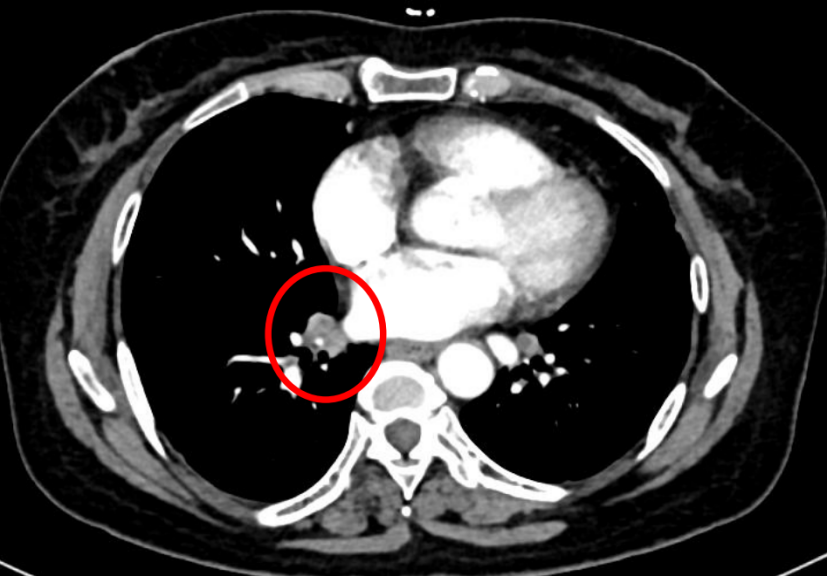

患者为女性,60岁,已绝经,既往史无特殊。2021年5月10日于院内行乳腺及淋巴结彩超检查,提示右乳腺实性结节(BI-RADS 4C级)及右腋下肿大淋巴结。进一步影像学评估显示,右乳原发灶大小约2.7×2.3 cm,右腋窝淋巴结约1.8×1.3 cm;同时可见双肺结节,最大约0.9×0.7 cm,并见右肺门淋巴结约1.1×1.0 cm。整体影像学结果提示患者初诊时已存在乳腺原发灶伴区域淋巴结及肺部转移。

图2:右腋窝淋巴结